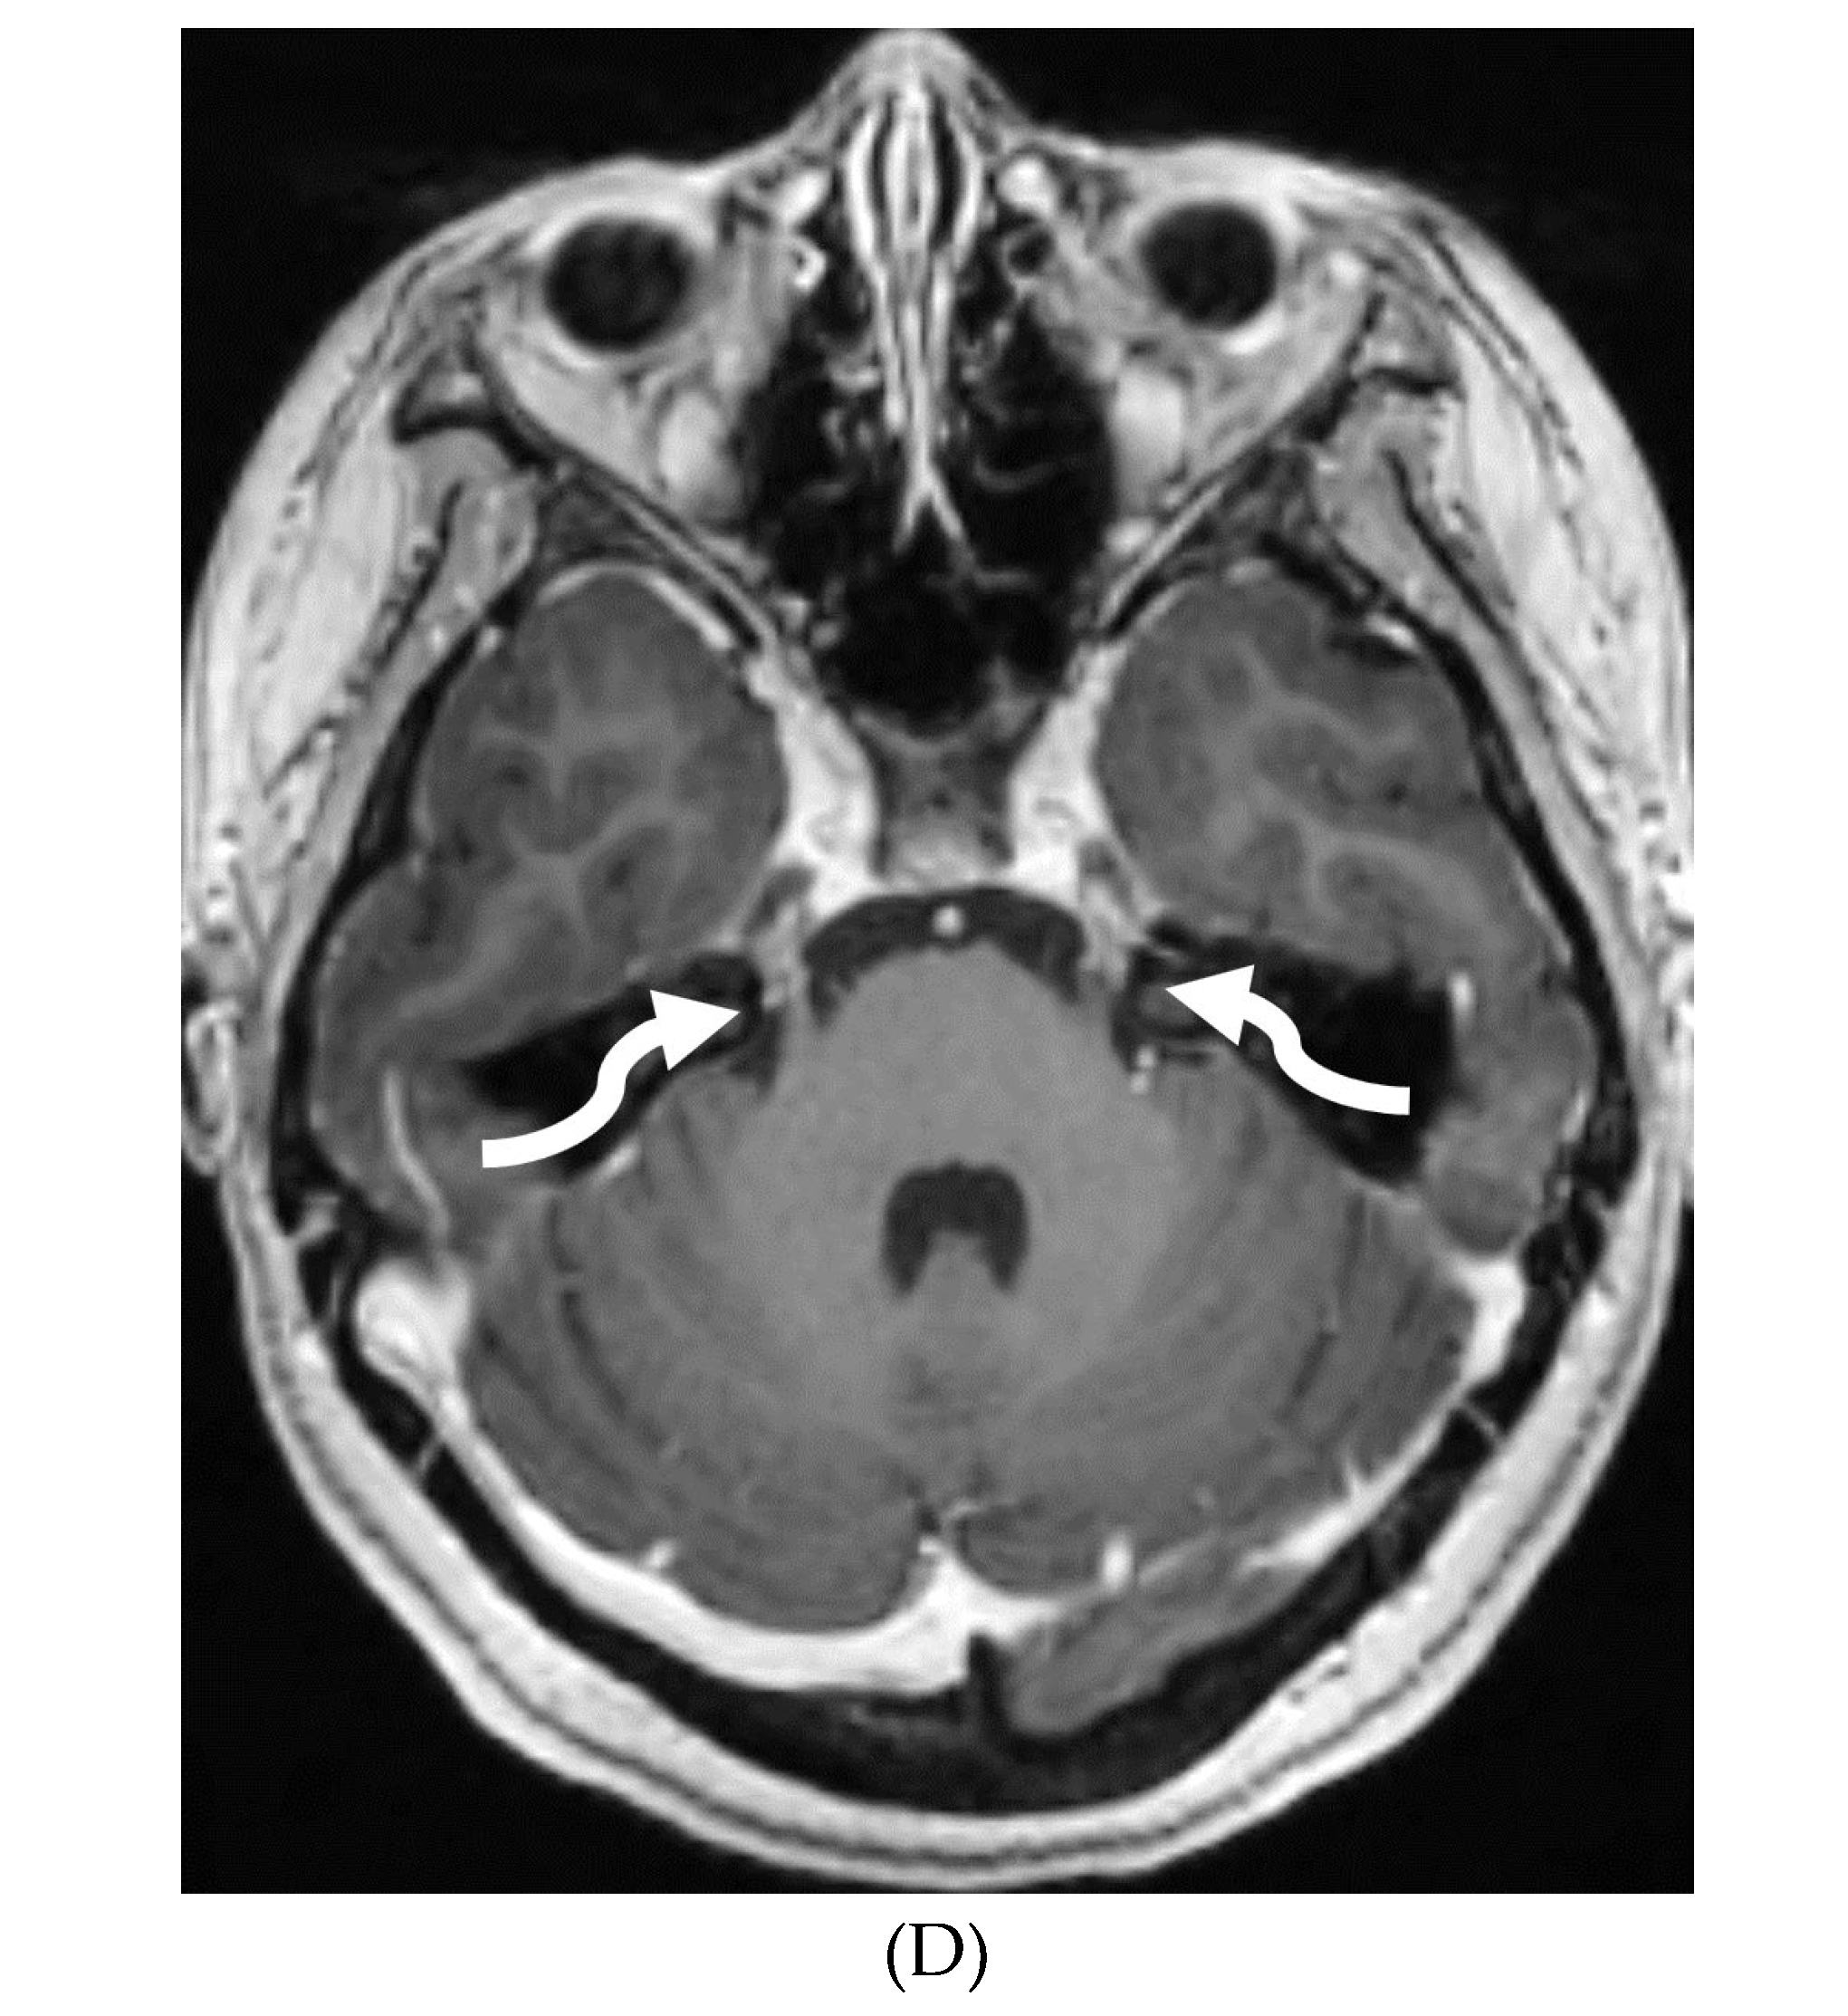

MOYA MOYA

- Liu ZW, Han C, Zhao F, Qiao PG, Wang H, Bao XY, Zhang ZS, Yang WZ, Li DS, Duan L. Collateral Circulation in Moyamoya Disease: A New Grading System. Stroke. 2019 Oct;50(10):2708-2715. Epub 2019 Aug 14. PMID: 31409266. [CrossRef]

- Tajmalzai A, Shirzai A, Najah DM. Early manifestation of Moyamoya syndrome in a 2-year-old child with Down syndrome. Radiol Case Rep. 2021 May 1;16(7):1740-1744. PMID: 34007395; PMCID: PMC8111440. [CrossRef]

- Horie N, Morikawa M, Nozaki A, Hayashi K, Suyama K, Nagata I. "Brush Sign" on susceptibility-weighted MR imaging indicates the severity of moyamoya disease. AJNR Am J Neuroradiol. 2011 Oct;32(9):1697-702. Epub 2011 Jul 28. PMID: 21799039; PMCID: PMC7965393. [CrossRef]

- Ohta T, Tanaka H, Kuroiwa T. Diffuse leptomeningeal enhancement, "ivy sign," in magnetic resonance images of moyamoya disease in childhood: case report. Neurosurgery. 1995 Nov;37(5):1009-12. PMID: 8559324. [CrossRef]

- Maeda M, Tsuchida C. "Ivy sign" on fluid-attenuated inversion-recovery images in childhood moyamoya disease. AJNR Am J Neuroradiol. 1999 Nov-Dec;20(10):1836-8. PMID: 10588105; PMCID: PMC7657767.

- Liu ZW, Han C, Wang H, Zhang Q, Li SJ, Bao XY, Zhang ZS, Duan L. Clinical characteristics and leptomeningeal collateral status in pediatric and adult patients with ischemic moyamoya disease. CNS Neurosci Ther. 2020 Jan;26(1):14-20. Epub 2019 Apr 13. PMID: 31875482; PMCID: PMC6930821. [CrossRef]

- Komiyama M, Nakajima H, Nishikawa M, Yasui T, Kitano S, Sakamoto H. Leptomeningeal contrast enhancement in moyamoya: its potential role in postoperative assessment of circulation through the bypass. Neuroradiology. 2001 Jan;43(1):17-23. PMID: 11214642. [CrossRef]